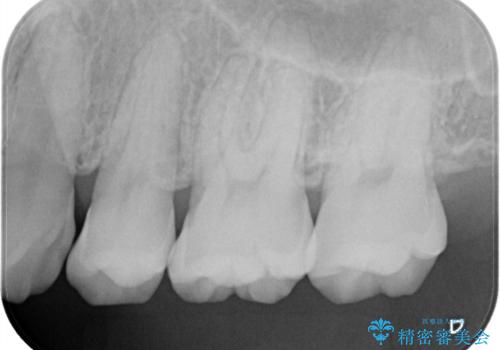

- 定期的にクリーニング(保険適応)に通って頂いている患者さんです。歯周ポケットが4ミリあったため歯茎を開いて歯石を除去するためにオープンフラップ術を行うことにしました。

歯周ポケットがそれほど深くない患者さんでしたが、いざ歯茎を開いてみるとそこにはたくさんの歯石がありました。もし歯周ポケットが4ミリだからと言って放置していれば数年後には、沢山の骨が無くなっていたことが予期出来ます。現段階で歯茎の下にある歯石を除去することにより骨が無くなることを予防する事が出来ました。